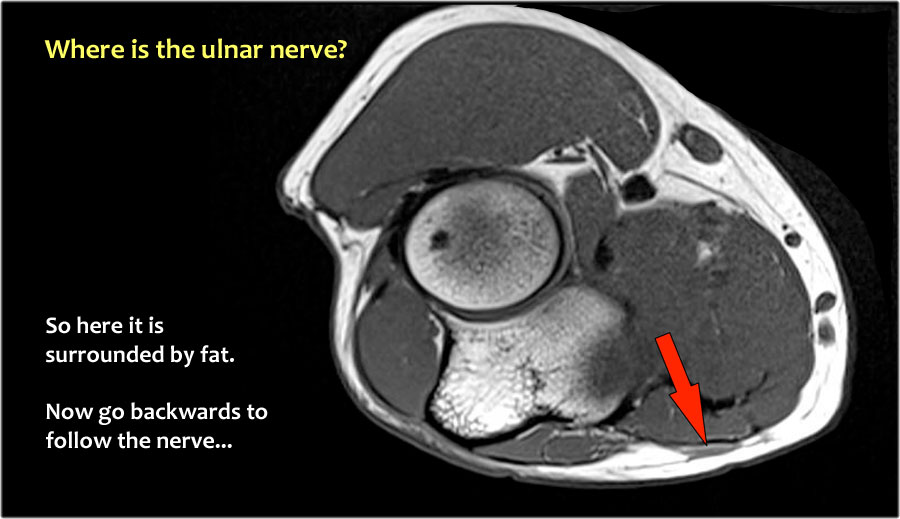

Một cách để thực hiện là đi theo các cấu trúc về phía xa cho đến khi tìm thấy dây thần kinh trụ ở phía xa tại vị trí bình thường của nó ở vùng cẳng tay gần được bao quanh bởi mô mỡ.

Sau đó khi bạn theo dõi nó về phía gần, bạn sẽ nhận thấy rằng đây là một trường hợp chuyển vị dưới da.